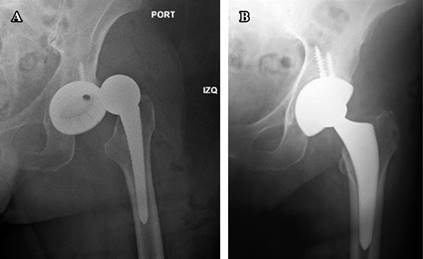

Early postoperative complications

Specifically, the three main early complications are dislocation, infection, and periprosthetic fractures. Early dislocations, as with any other approach to the hip, are usually a product of component mispositioning. Unless the acetabular or femoral components have been considerably retroverted upon implantation, dislocations following the DAA are typically anterior. Due to the musculature not being detached posteriorly or anteriorly, as long as the components are well positioned, it is postulated that this approach enhances inherent stability compared with other approaches. Reported dislocation rates reported in the literature were 0.96 to 1.5%. These rates are significantly lower than the rates generally quoted for other approaches22,23 (Figure 6A-B).